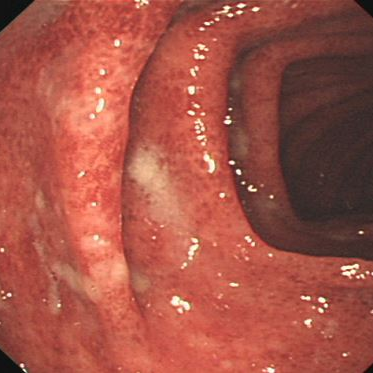

反复血尿2个月,49岁男子查出"百万分之一"罕见癌!

49岁的王先生(化名)从未想过,自己反复出现的无痛性血尿,会牵出一个“隐匿杀手”,并最终指向一个连泌尿外科医生都极少遇见的恶性肿瘤——脐尿管癌。